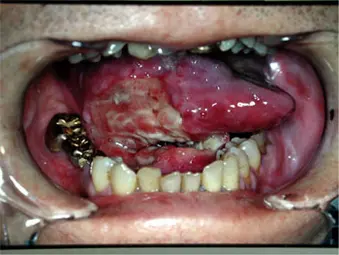

口腔がんの種類には次のようなものがあります

- 癌腫(がんしゅ)

舌がん、歯肉がん、唾液腺がん、など - 肉腫(にくしゅ)

1位 舌がん・・・約60%

2位 歯肉がん

3位 口底がん

3位 頬粘膜がん